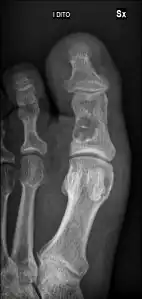

Unprovoked break in big toe, with "fallen leaf" sign.